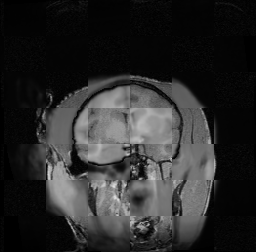

For each of the 10 subjects, we show checkerboard slices in each direction (1) before registration, first row; (2) after rigid->scaleversor->affine registration, second row; and (3) after BSpline registration, third row.

Issac

Issac is a good example of BSpline registration failure.

Ron noted, the reason might be that Issac had his mouth open, unlike most of the subjects registered successfully.